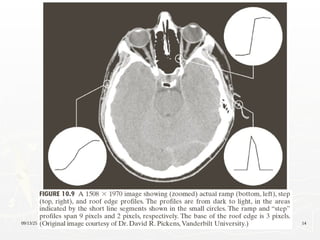

Characteristics of First and Second Order

Derivatives

► First-order derivatives generally produce thicker edges

in image

► Second-order derivatives have a stronger response to

fine detail, such as thin lines, isolated points, and noise

► Second-order derivatives produce a double-edge

response at ramp and step transition in intensity

► The sign of the second derivative can be used to

determine whether a transition into an edge is from

light to dark or dark to light